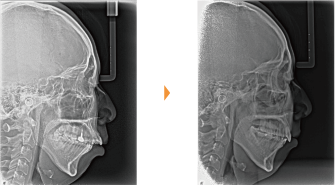

| 主訴 | 上の前歯が出ている、下の前歯がでこぼこ |

| 年齢・性別 | 20歳 / 女性 |

| 治療方針 | 上下顎前歯部に叢生があり、オーバージェットが大きい上顎前突。下顎の時計回りの回転が著しく下顎の後退感が強い。プロファイルの改善は困難が予想される。 |

| 抜歯部位 | 小臼歯4本抜歯 |

| 使用装置 | マルチブラケット装置、トランスパラタルアーチ、歯科矯正用アンカースクリュー |

| 治療期間 | 34か月 |

| リテーナー | 上顎インビジブル、下顎スプリングリテーナー |

| 費用 | 885,000円(税別) |